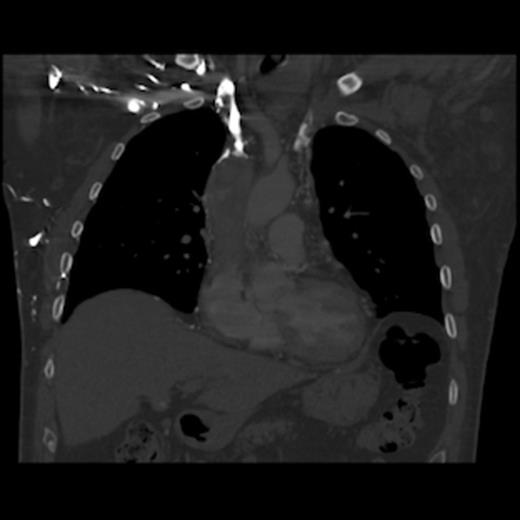

A 67-year old gentleman presented with progressive head and neck swelling and discomfort for several months. His symptoms were pronounced by bending over or straining in the bathroom. His symptoms worsened and he was referred for thoracic surgery consultation after a mass was seen on chest x-ray. He was diagnosed with SVC syndrome secondary to a mediastinal mass, demonstrated best by computed tomography (CT) [Figures 1, 2, 3].

CT of the chest (coronal section) with intravenous contrast: demonstrates large thrombus obstructing the superior vena cava down to the right atrium